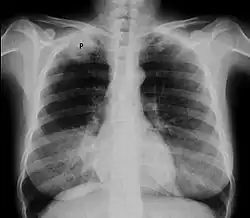

Chest X-ray showing a Pancoast tumor (labeled as P, non-small cell lung carcinoma, right lung), from a 47-year-old female smoker.

A Pancoast tumor is a tumor of the apex of the lung. It is a type of lung cancer defined primarily by its location situated at the top end of either the right or left lung. It typically spreads to nearby tissues such as the ribs and vertebrae. Most Pancoast tumors are non-small-cell lung cancers.

Diagnosis of a Pancoast tumor can be difficult in the early stages to the similarity of its symptoms with other conditions such as arthritis, with shoulder pain being one of the only symptoms that might indicate further imaging for a patient.[14] Though a chest x-ray is a good screening test and might be the first mode of imaging used, they are not easily seen during the early stages of the disease due to their size and location in the chest.[15]